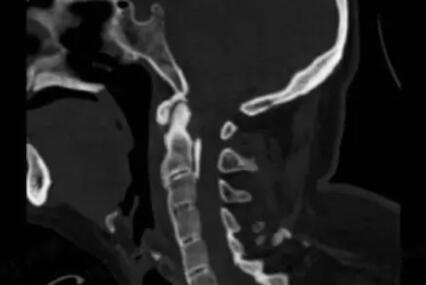

上周,刘女士与亲友在富阳享受漂流乐趣时,不料遭遇急流冲击,颈椎遭受重创。强烈的疼痛感迅速蔓延全身,四肢逐渐失去力量,最终不幸全身瘫痪。医生诊断为颈椎骨折导致脊髓严重损伤,更揭示出她早有强直性脊柱炎病史,这一慢性疾病让她的脊柱如脆骨般易碎。浙大二院的及时手术虽挽回生命,却难以逆转瘫痪的事实。